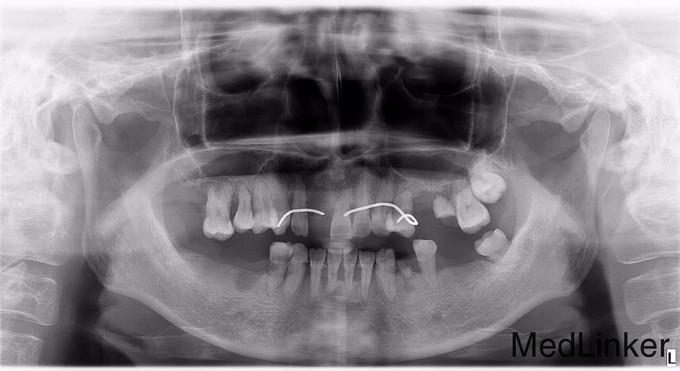

口内多颗牙拔除,要求镶牙

左上后牙多颗牙缺失